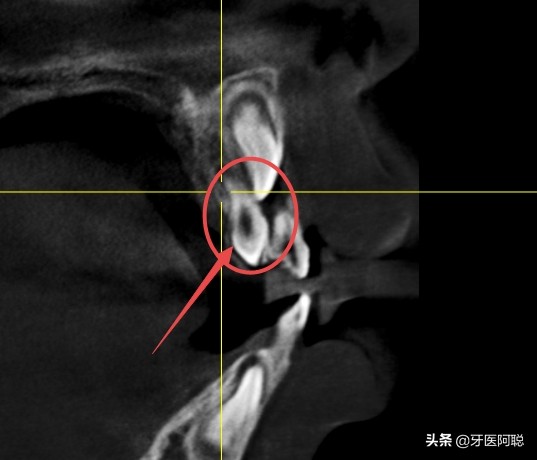

在儿童换牙期间,一旦发现有形态异常的牙时应请医生确诊。上颌门牙区的多生牙,若在门牙未萌出之前及早拔除,可以防止上门牙的错位生长。若该牙没有及时拔除,在门牙萌出后发现前牙拥挤畸形或门齿前突畸形,此时一定要拔除多生牙,让前牙自行调整。也可以戴矫正器或皮圈矫正。总之,多生牙是额外牙齿,在其刚一萌出,看其外观不正常,在拍牙片,认定为畸形多生牙后,应及早拔除。